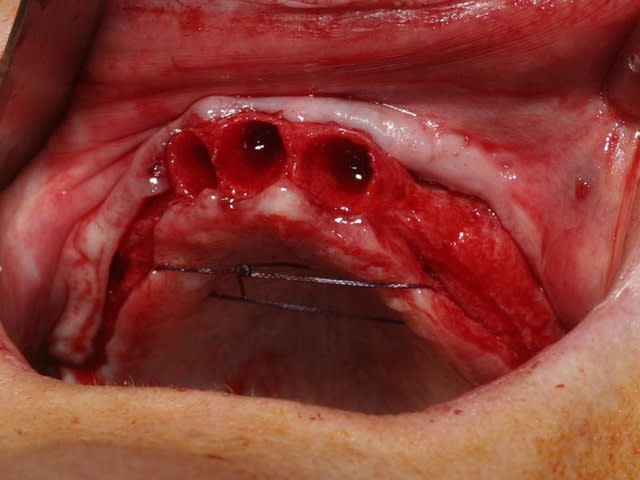

bon, toujours aussi speed je suis, mais après certaines réclamations, et malgrès ma réticence à poser un cas non "consolidé", voici en avant première mon premier all on 4, version photos ratées et non retouchées, mais... speed je suis je vous disais ;)

sto le bla bla, et pasons le diaporama... bon voyage au pays de la mise en charge immédiate totale au maxillaire de fille carole sur dame ginette, une patiente en or que j' adore, et pour qui je suis très très heureuse d' avoir pu réaliser cette chirurgie et la première étape prothétique.....

Tu as vraiment bien réussi à longer le plancher sinusal et apparemment la patiente pourra se pendre aux implants...

Tu as utilisé des Nobel Speedy si je ne me trompe pas.

Peux tu nous en dire un peu plus sur les implants, leurs diamétres et leur longueurs ?